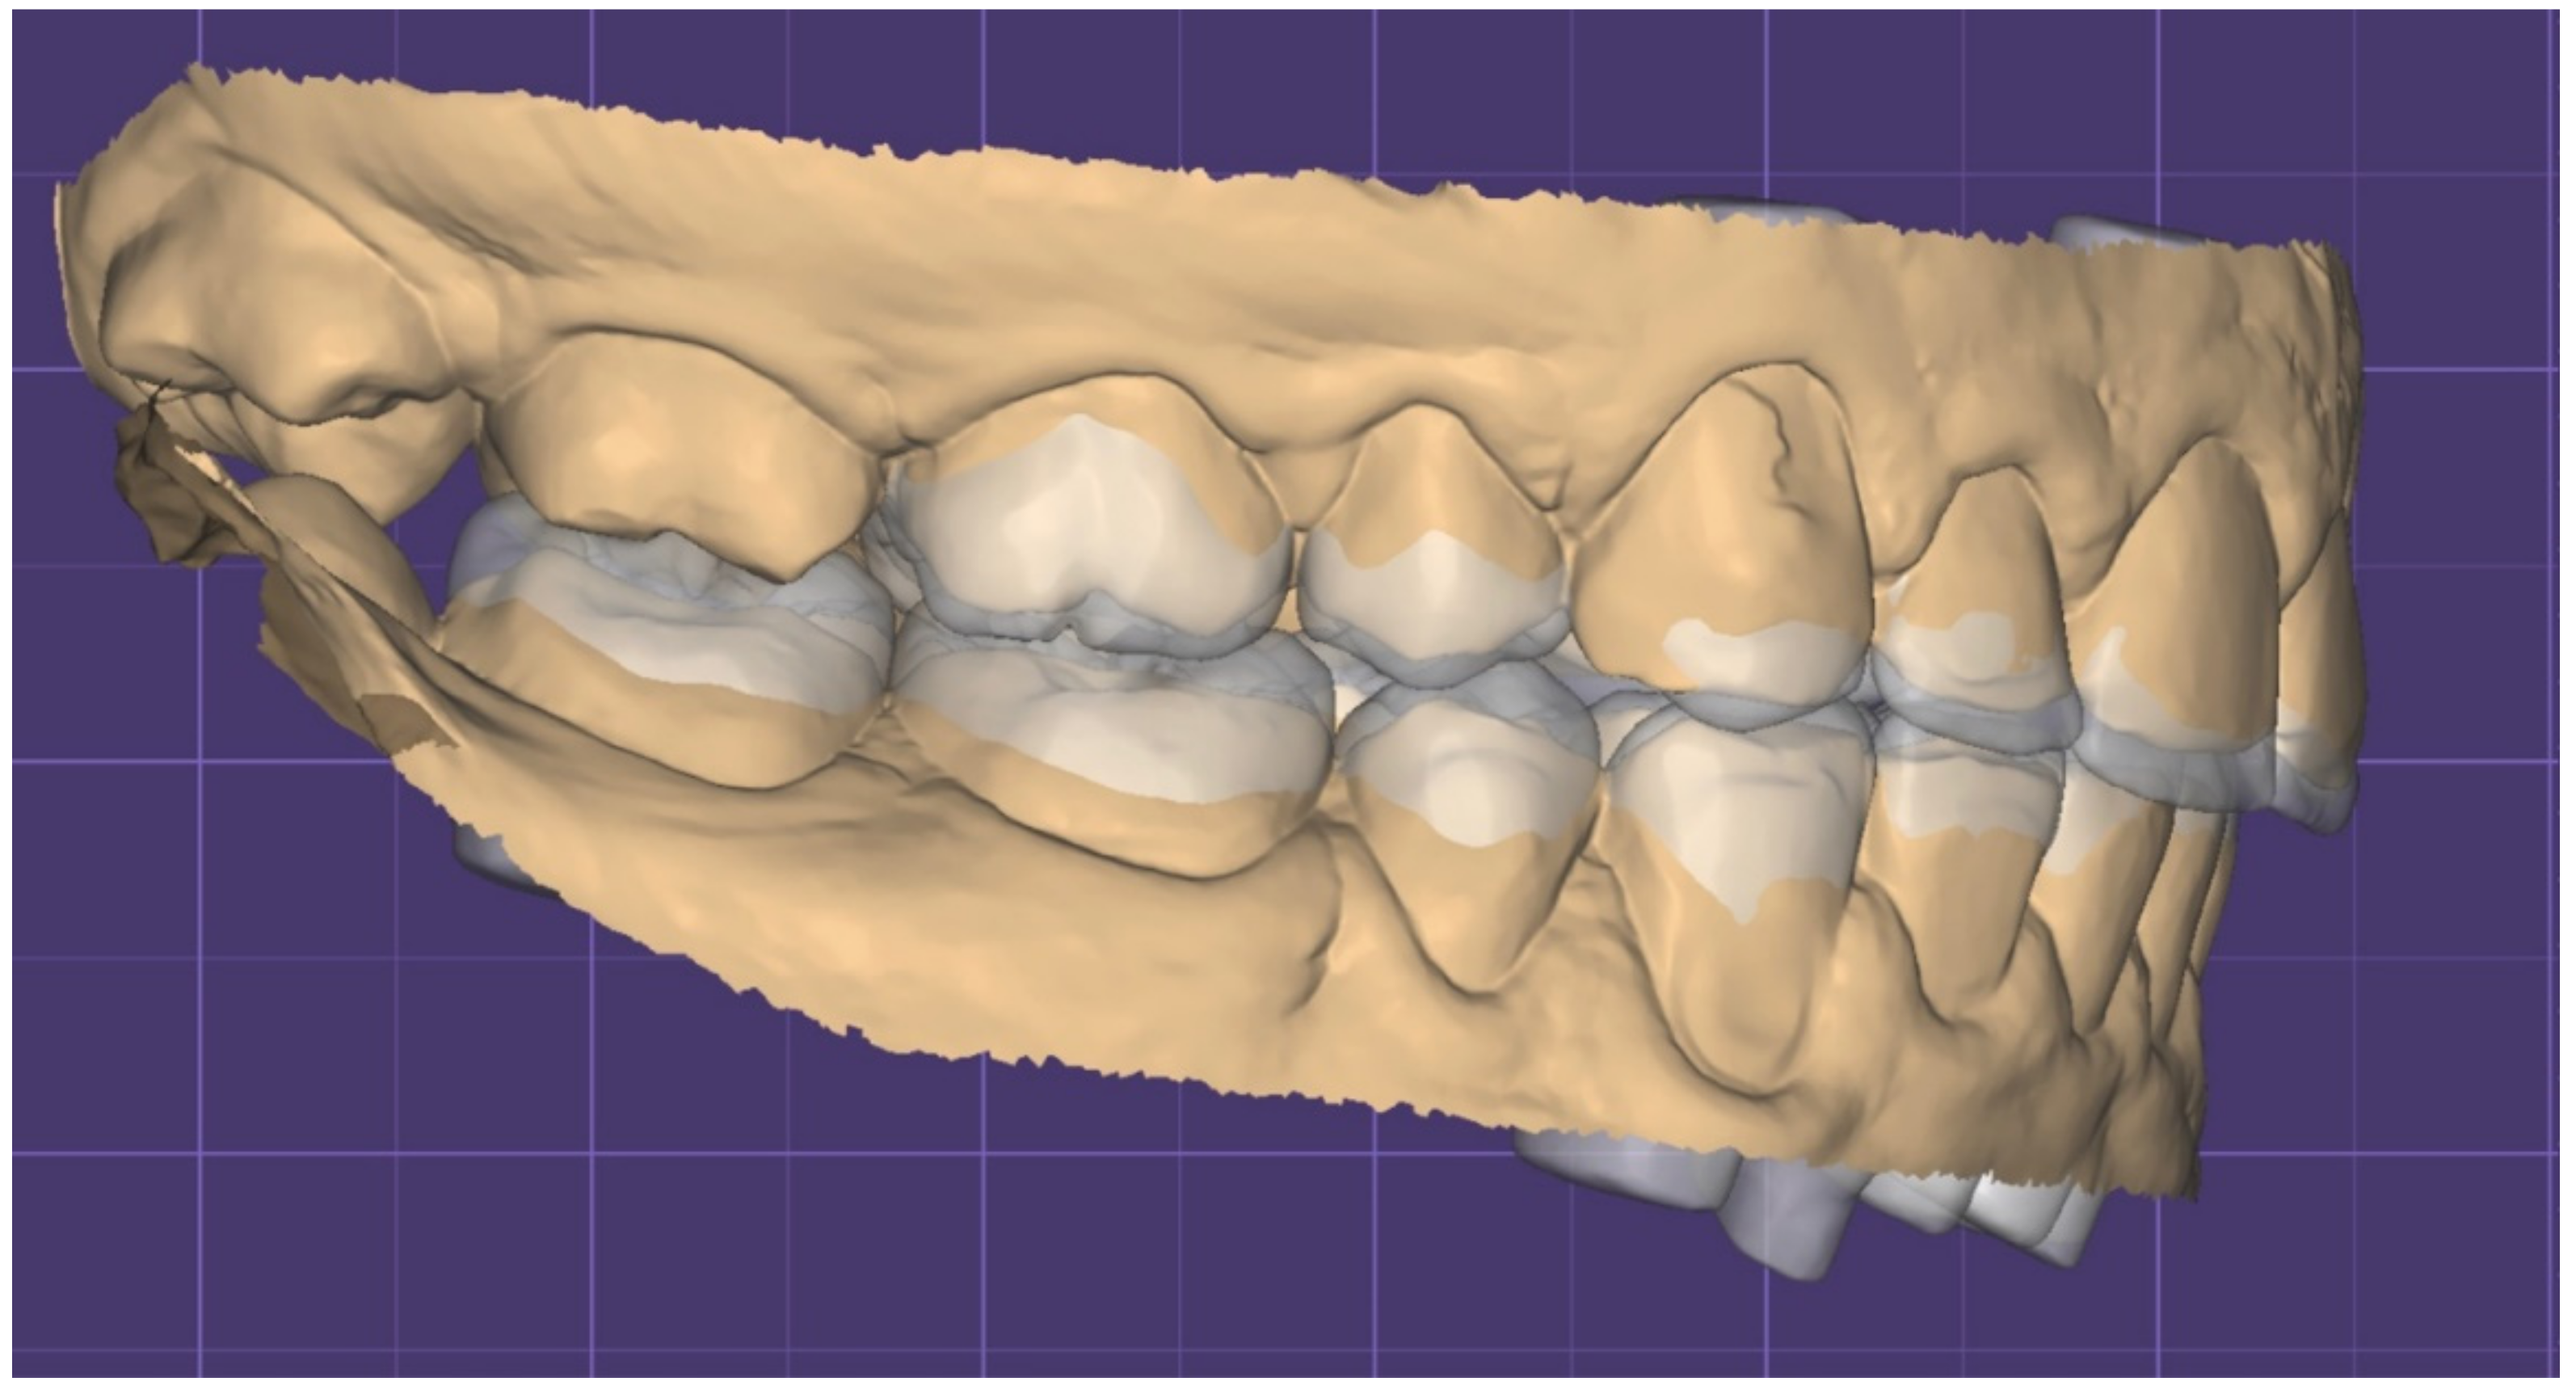

2.1. Planning Phase

2.2. Restorative Phase